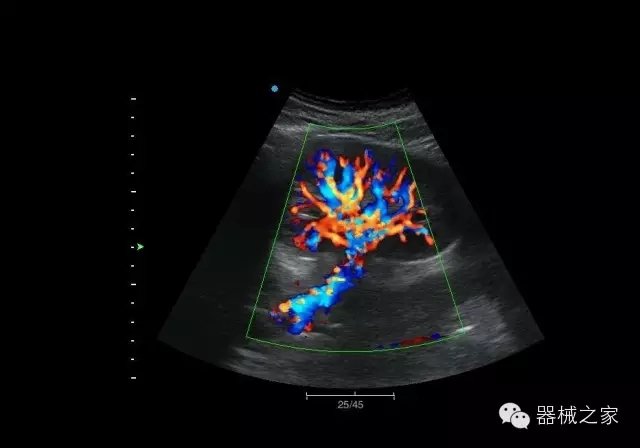

臨床圖片賞析

結(jié)甲

腎臟血流

肝血管瘤

產(chǎn)品特點(diǎn)

·屏幕可左右90度旋轉(zhuǎn);

·雙模操控;

·兩用提手;

·雙鋰電池;

·超輕機(jī)身;

·15寸高亮高清醫(yī)學(xué)顯示器;

·衛(wèi)星布局操控面板;

·一體化剪切板;

·多功能導(dǎo)航鍵;

“宏云”平臺

·采用移植自高端臺式彩超的“宏云”平臺技術(shù),使系統(tǒng)具有更優(yōu)秀的圖像效果;

人性化的設(shè)計(jì)

·內(nèi)置電池,輕巧的外觀設(shè)計(jì)以及臨床功能、軟硬件設(shè)計(jì)的人性化設(shè)計(jì),使系統(tǒng)在臨床多科室移動(dòng)診查中,均從容應(yīng)對;

Fusion THI二代融合諧波成像

·在不同諧波頻率段獲得的信息進(jìn)行實(shí)時(shí)融合,既能獲得諧波圖像分辨率又能提高圖像的穿透力,降低圖像噪音;

XBeam多域復(fù)合成像

·通過頻域和空域角度進(jìn)行復(fù)合的圖像處理,能有效消除由于圖像離散化和圖像衰減引起的空間分辨率下降的不利影響,彌補(bǔ)原有圖像空間分辨率的不足,獲得更加清晰的圖像;

CFDA注冊證編號

·粵食藥監(jiān)械(準(zhǔn))字2014第2231316號